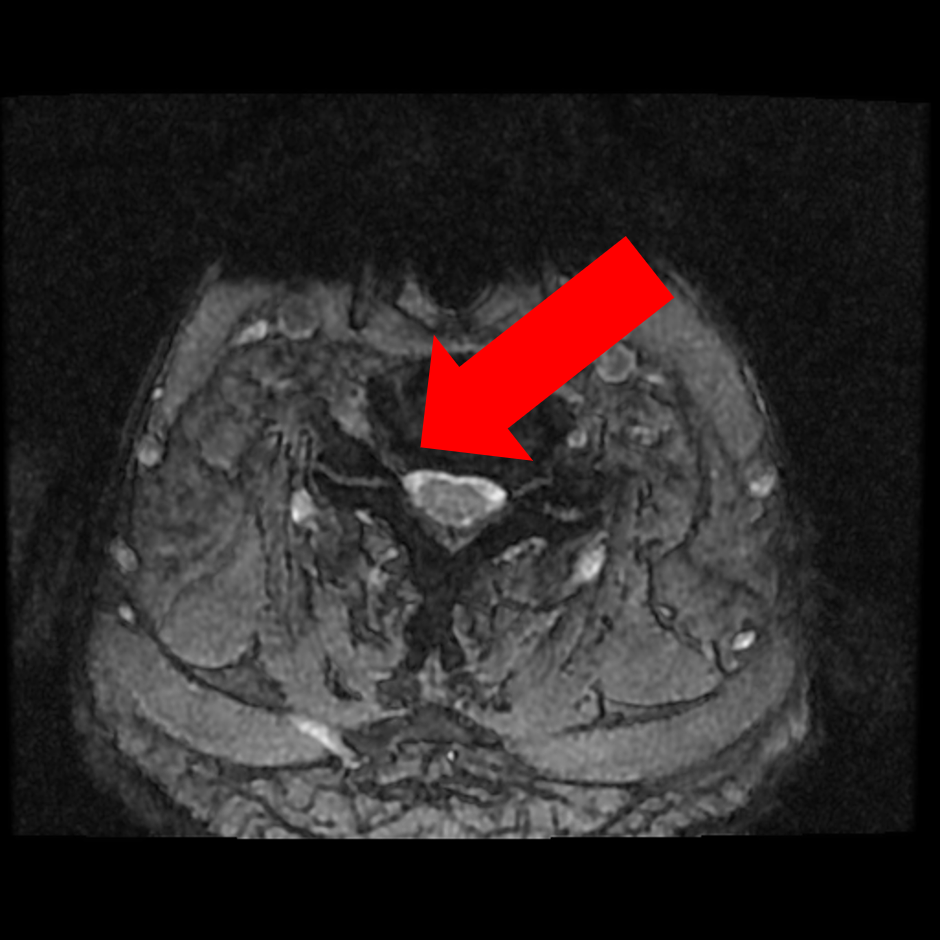

圖二、【術前評估】第五、第六頸椎椎間盤突出往後擠壓到脊髓腔(如左圖箭頭)、椎間盤突出往後偏右擠壓到第六條神經(如右圖箭頭)。

圖三、【術前評估】第六第七頸椎間盤突出往後擠壓到脊髓腔(如左圖箭頭)、同時顯示椎間盤突出往後偏右已擠壓到第七條神經(如右圖箭頭)。